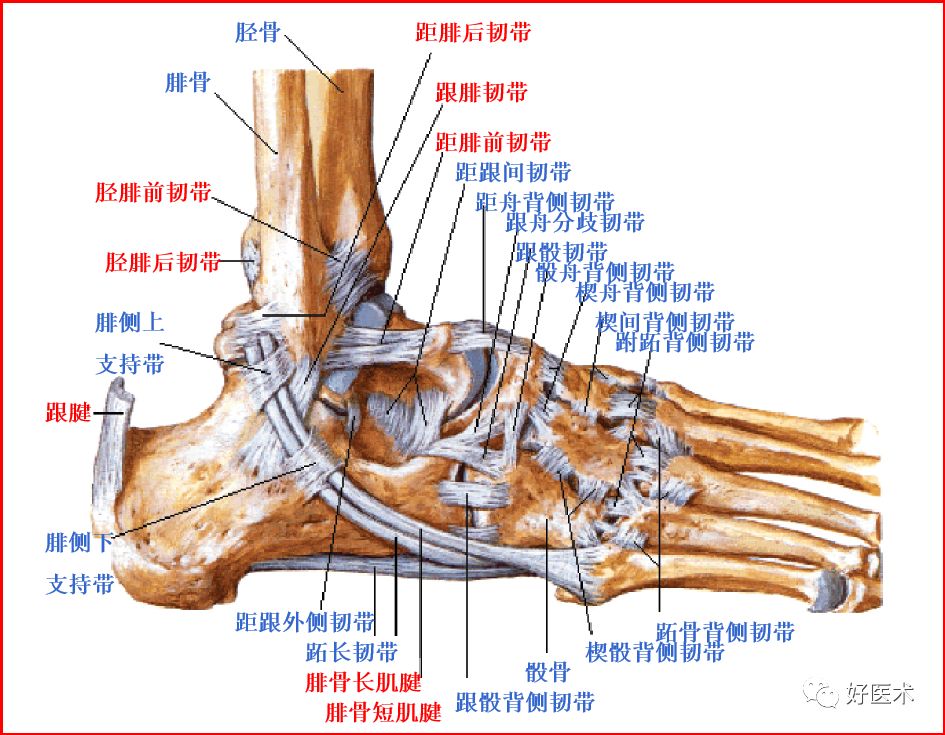

一、解剖和扫描方法

踝关节的韧带

联合韧带

外侧副韧带

三角韧带

距跟韧带

胫腓前后韧带:位于胫距关节上方,连接外踝前、后面与胫骨前、后结节,起支持作用

胫腓横韧带:位于胫腓后韧带前下方,后外踝延伸至胫骨关节面后缘,恰好位于内踝的外侧

距腓前韧带

距腓后韧带

跟腓韧带